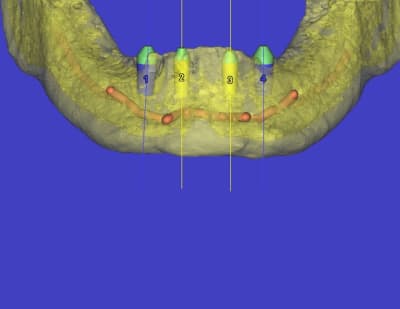

ah, celle là, je l'attendais...c'est court parce qu'il y a, après étude du scan...un gros, très gros canal incisif qui passe juste dessous...et qui donne un foramen mentonnier dans la zone antérieur...bien identifié...du genre à contenir un faisceau sensitif pour le menton et la partie médiane de la lèvre...tu vois ce que je veux dire...???

pour ce cas, j'ai posé en 34 et 44 des 4x8...et pour 32 et 42 des 4x10...

pour la gamme on a des 3.4mm en 8, 10 et 12mm

des 4mm et 5mm en 7, 8, 10 et 12mm...

sur le "standard" en 4 et 5mm les plates-formes prothétiques sont sous dimensionnées (gum launching pad...un genre de platform switching) pour le 4 on a une plateforme de 3,4mm et de 4mm pour le 5mm...

pour répondre à une autre de tes questions..."pourquoi pas les expanseurs"...simple...la bourde...l'assistante qui oublie de les mettre à stériliser...mais bon y manque pas grand chose en vestibulaire...et c'est aussi pourquoi j'ai mis des 4mm en 34 et 44...à l'origine je voulais mettre des 5mm...